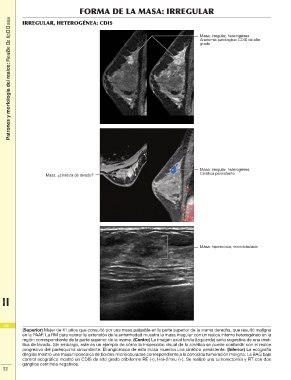

Patrones y morfología del realce: Realce de tipo masa FORMA DE LA MASA: IRREGULAR

IRREGULAR, HETEROGÉNEA: CDIS

Masa: ¿cinética de lavado? Masa: irregular, heterogénea

Cinética persistente

Masa: hipoecoica, microlobulada

(Superior) Mujer de 41 años que consultó por una masa palpable en la parte superior de la mama derecha, que resultó maligna

en la PAAF. La RM para valorar la extensión de la enfermedad muestra la masa irregular con un realce interno heterogéneo en la

región correspondiente de la parte superior de la mama. (Centro) La imagen axial tardía (izquierda) sería sugestiva de una ciné-

tica de lavado. Sin embargo, este es un ejemplo de cómo la inspección visual de la cinética se puede confundir con el realce

2 progresivo del parénquima circundante. El angiomapa de esta masa muestra una cinética persistente. (Inferior) La ecografía

dirigida mostró una masa hipoecoica de bordes microlobulados correspondiente a la conocida tumoración maligna. La BAG bajo

control ecográfico mostró un CDIS de alto grado cribiforme RE (+), Her-2/neu (+). Se realizó una tumorectomía y RT con dos

ganglios centinela negativos.